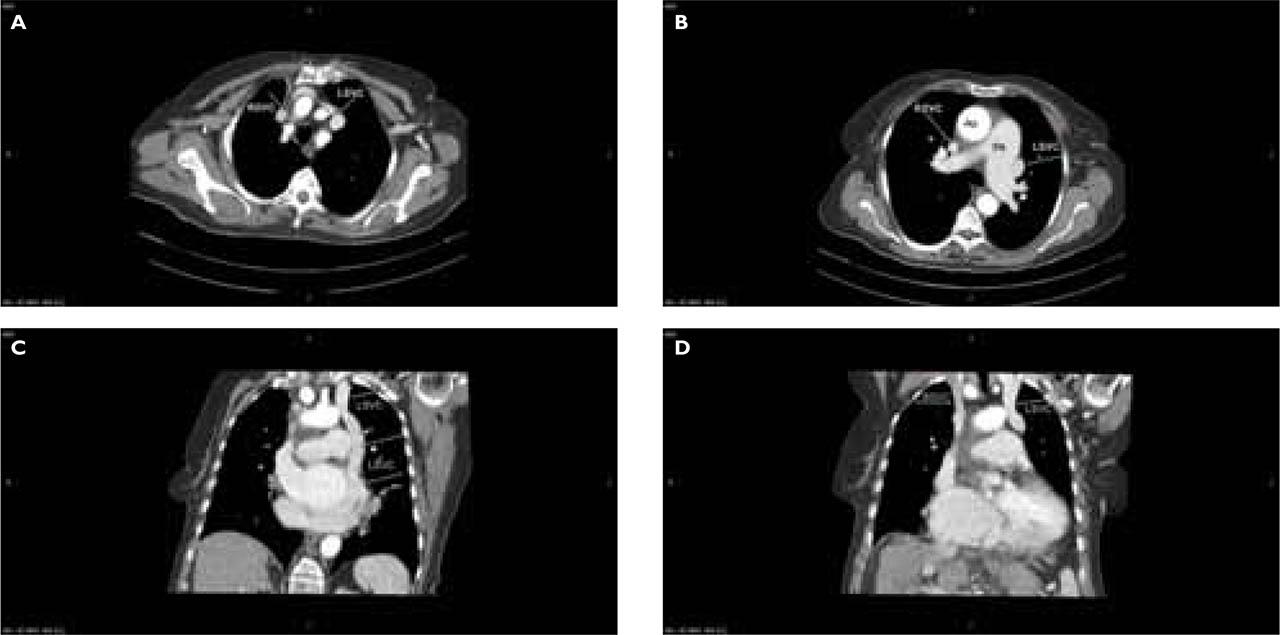

Figure 3

A. Thoracic CT angiography, axial section, mediastinal view shows RSVC and LSVC with a communicating vein of 8 mm (CV) between the sternum and great vessels (green arrows). B. Thoracic CT angiography, axial section, mediastinal view: dilated main, right and left PA, aorta (Ao), LSVC between Ao and LPA, the RSVC in normal position (green arrows). C. Thoracic CT angiography coronal section, mediastinal view: brachiocephalic trunk continues with persistent LSVC (22/18 mm – AP/T) which descends lateral from the aortic arch, LPA, LA and anterior from left inferior pulmonary vein (green arrows), joining the CS which is grossly dilated in calibre and draining into RA. D. Thoracic CT angiography coronal section, mediastinal view: RSVC draining in the RA, partially visible LSVC (green arrows).